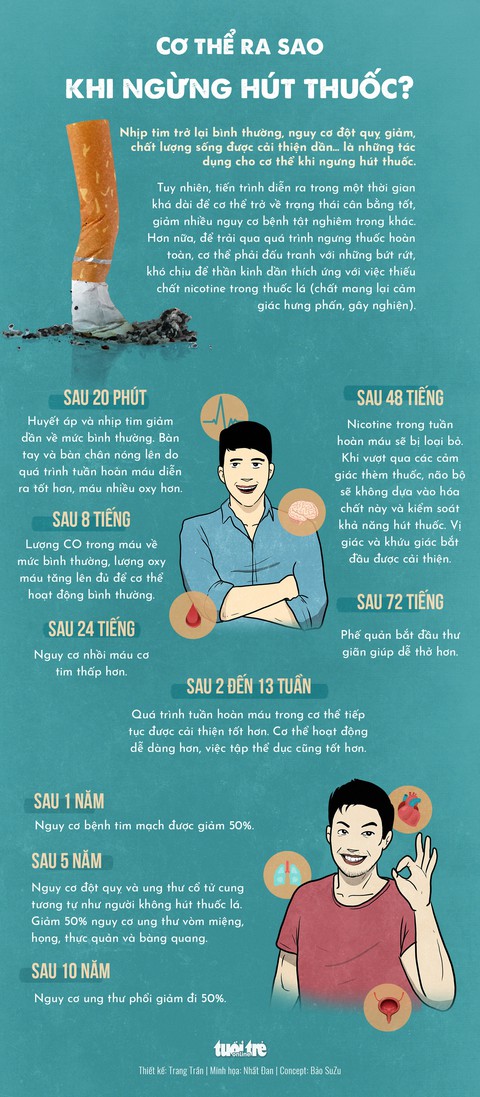

TTO - Nhịp tim trở lại bình thường, nguy cơ đột quỵ giảm, chất lượng sống được cải thiện dần… là những tác dụng cho cơ thể khi ngưng hút thuốc.